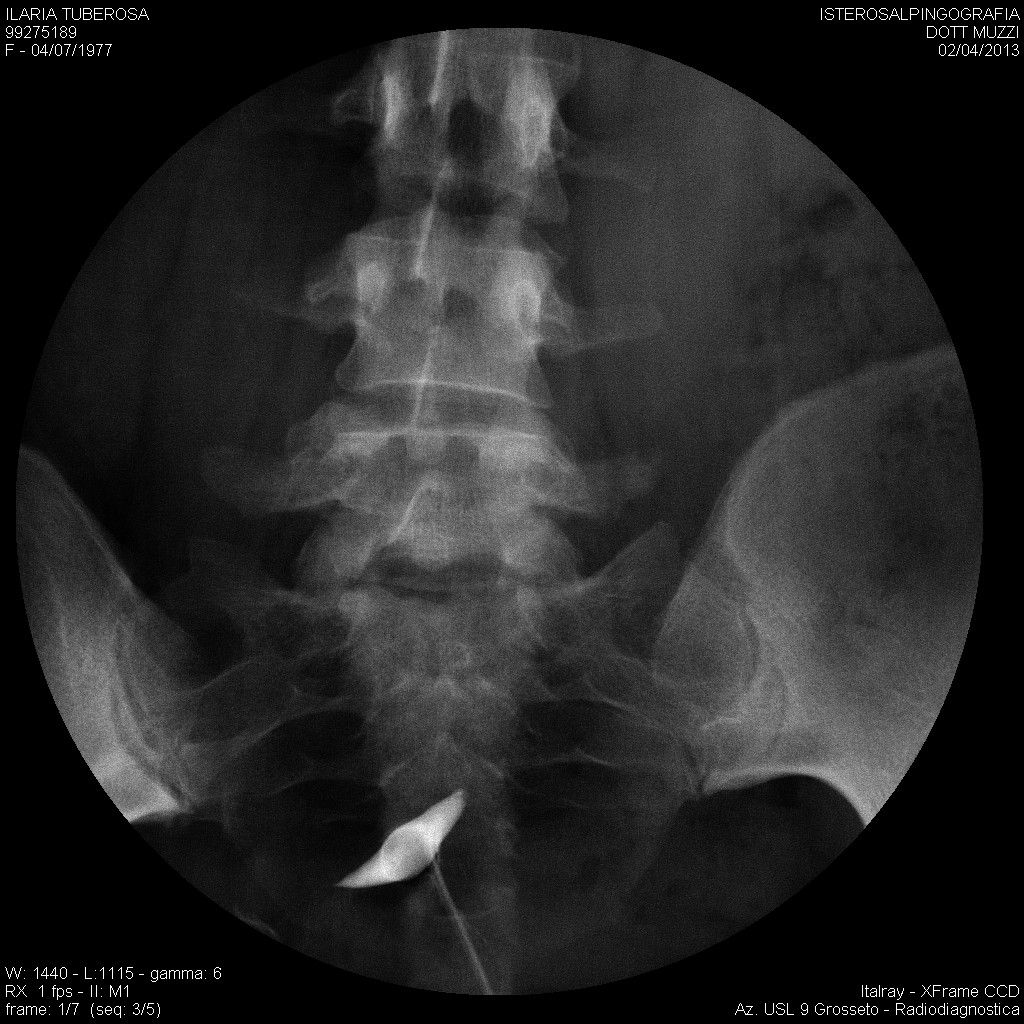

mi ritrovo a mettere in discussione un isterosalpingografia del 2013, dopo che per caso un medico radiologo la scorsa settimana ha guardato l'esame e mi ha detto che sembrerebbe pervia la tuba destra, al contrario di quanto recita il referto.

Vi allego immagini estrapolate dal cd nella speranza possiate aiutarmi nella lettura.

im000004.jpg

[ 154.88 KiB | Osservato 507 volte ]